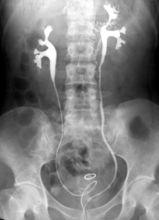

逆行腎盂造影逆行腎盂造影:是經膀胱將輸尿管,注入造影劑,使腎盞、腎盂、輸尿管顯影。目前,逆行腎盂造影可在電視監控下進行,可將導管尖端放到任何需要部位,從而得到最滿意的填充。

逆行腎盂造影的優點是腎盂、腎盞充盈良好,顯影清晰,有利於對細微結構解剖的觀察;對腎功能不良的病例仍能使其顯影;行膀胱檢查時,還可以了解膀胱及輸尿管的情況。主要缺點是創傷性檢查,可引起痙攣、腎絞痛,且有上行性感染的危險,故臨床上,一般僅用於靜脈腎盂造影達不到診斷目的的病例檢查。